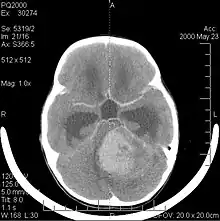

La tomodensitométrie (TDM) et L'imagerie par résonance magnétique (IRM) peuvent détecter efficacement une néoplasie dans le cerveau. L'IRM est plus sensible que la TDM pour identifier les lésions, mais présente des contre- indications pour les patients porteurs de stimulateurs cardiaques, de prothèses incompatibles, de clips métalliques et contre-indications. La TDM reste la méthode de choix pour détecter les calcifications au sein des lésions ou les érosions osseuses de la calotte ou de base du crâne. L'utilisation d' agents de contraste, iodés dans le cas du scanner et paramagnétiques (gadolinium) dans le cas de l'IRM, permet l'acquisition d'informations sur la vascularisation et l'intégrité de la barrière hémato-encéphalique, une meilleure définition de la tumeur tumorale par rapport à l' œdème environnant et à la génération d' hypothèses sur le degré de malignité. L'examen radiologique permet également d'évaluer les effets mécaniques et les modifications importantes des structures cérébrales résultant de la tumeur, telles que l' hydrocéphalie et les hernies, dont les effets peuvent être fatals. Enfin, en préparation à la chirurgie, ce diagnostic peut être utilisé pour déterminer la localisation de la lésion ou l'infiltration de la tumeur dans des zones vitales du cerveau. À cette fin, l'IRM est plus efficace que la tomodensitométrie car elle peut fournir des images en trois dimensions.

Les outils d'imagerie radiologique diagnostique mettent en évidence la modification du tissu néoplasique par rapport au parenchyme cérébral normal (par le biais de modifications de la densité tissulaire imagée électroniquement en TDM et de l'intensité du signal en IRM). Comme la plupart des tissus pathologiques, les tumeurs sont également reconnaissables par une accumulation accrue d'eau intracellulaire. Dans la tomodensitométrie, ils apparaissent hypodenses, c'est-à-dire de moindre densité que le parenchyme cérébral, dans la tomographie par résonance magnétique nucléaire avec relaxation spin-réseau hypointense et en relaxation spin-spin ainsi que l' hypersignal en pondération protonique (PD).

La tomodensitométrie du cerveau montre généralement une masse tissulaire qui peut être améliorée par l'un ou l'autre contraste. Au scanner, les gliomes de bas grade apparaissent généralement isodenses au parenchyme normal et peuvent donc ne pas présenter de rehaussement de contraste. De même, les lésions de la fosse crânienne postérieure sont difficiles à identifier au scanner. Par conséquent, les seuls résultats d'une telle tomographie ne sont pas toujours suffisants à des fins diagnostiques. Dans les cas douteux, l'utilisation de l'imagerie par résonance magnétique plus sensible est indispensable.

Sur-L'IRM montre une tumeur intracrânienne comme une lésion massive qui peut devenir plus luminescente après utilisation du produit de contraste. Cependant, il y a toujours une anomalie de signal dans -L'imagerie par résonance magnétique, qui indique la présence d'une néoplasie ou d'un œdème vasogénique. Habituellement, une luminescence accrue (amélioration du contraste) indique une tumeur d'un grade supérieur de malignité. Un anneau de contraste est caractéristique du glioblastome, avec la partie luminescente correspondant à la partie vitale de la tumeur maligne, et la plus foncée - zone hypointense correspondant à une nécrose tissulaire.